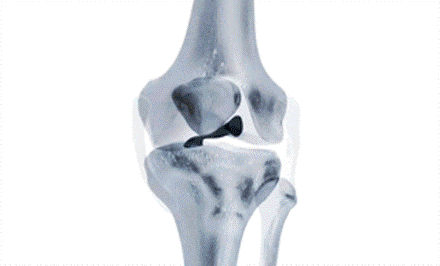

I.D.E.A.L. femoral tunnel location (黑色圆圈位置为理想股骨骨道位置)。

术后X线